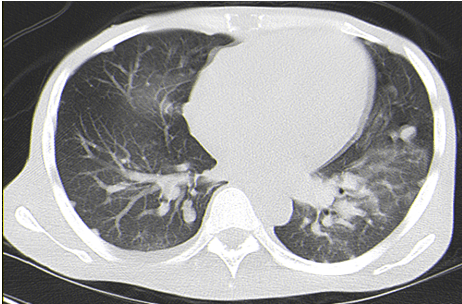

The patient was able to follow-up with oncology and was begun on chemotherapy, specifically carboplatin and etoposide for two cycles. At that point the patient was readmitted and had a follow-up CT scan of the abdomen and chest (Figure 2) and (Figure 3), which showed worsening of his disease. The patient continued to deteriorate and succumbed to the disease six months after diagnosis.

Figure 3: CT scan of the chest for follow-up. This CT done at the same time as Figure 2 shows the significant bilateral pulmonary metastases from his disease.